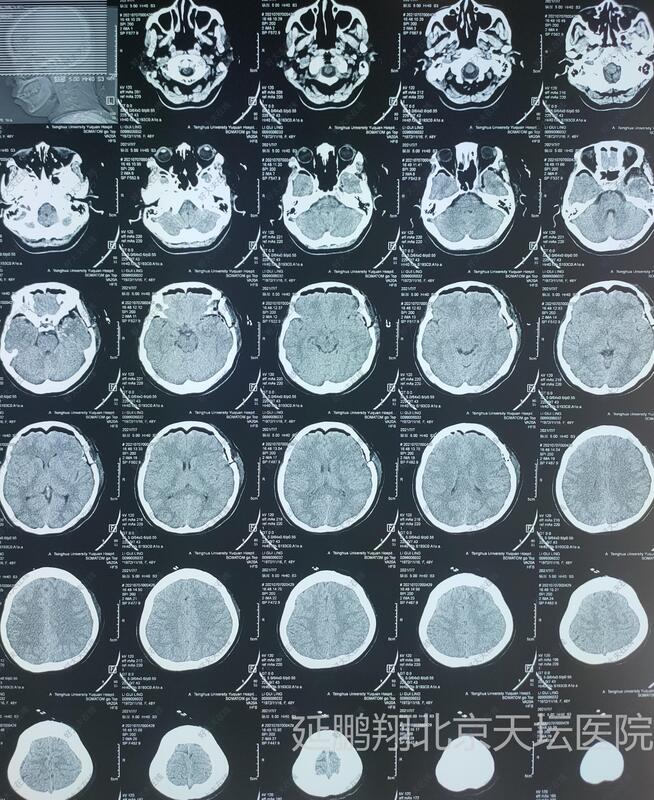

- 治疗后1天

术后病人全麻苏醒顺利,生命体征平稳,四肢活动好。常规术后六小时复查头颅CT显示肿瘤消失。